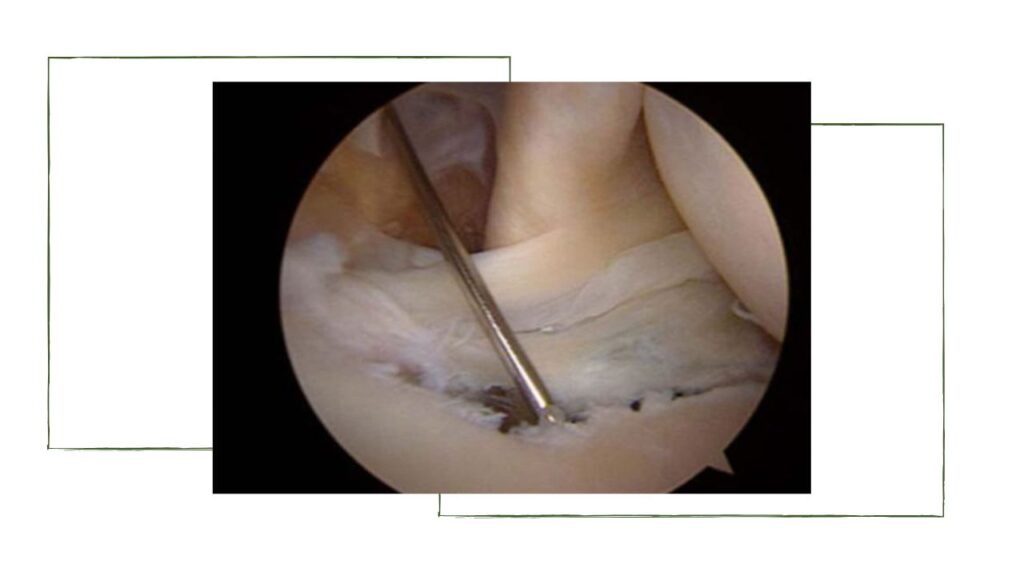

A vídeo-artroscopia para a correção da lesão de Bankart, desenvolvida pela escola americana.

A cirurgia de Bankart realizada por vídeo-artroscopia tem a vantagem da técnica menos invasiva e que não muda a anatomia, no entanto é menos eficaz para lesões ósseas maiores ou com mais recidivas. Outras técnicas artroscópicas podem ser associadas como o fechamento da lesão de Hill Sachs (Remplissage), e a utilização do tendão longo do biceps para fixar na reparo (DAS).